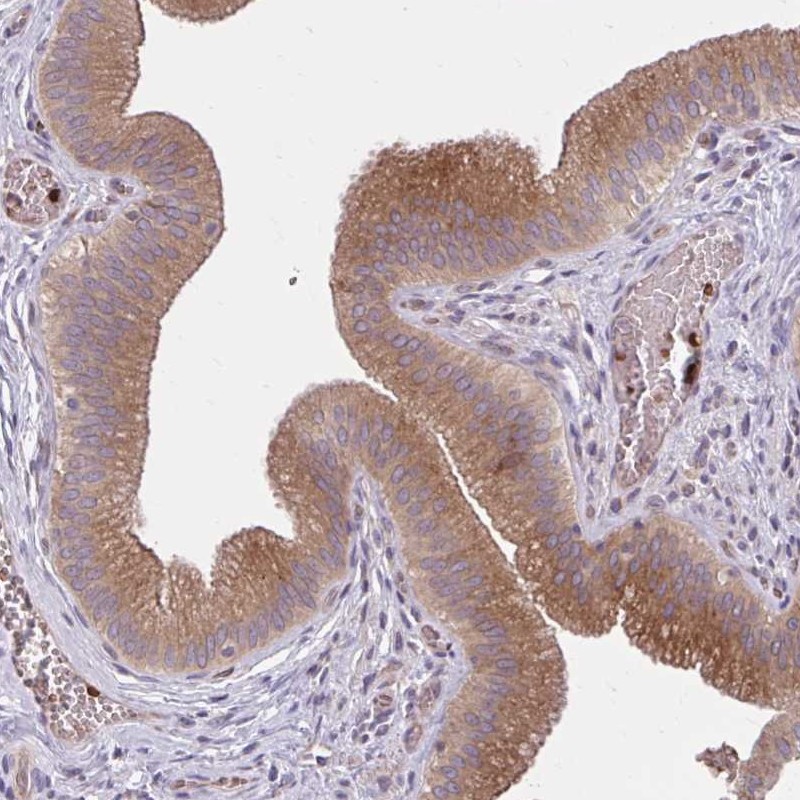

Immunohistochemical staining of human gallbladder shows strong cytoplasmic positivity in glandular cells.